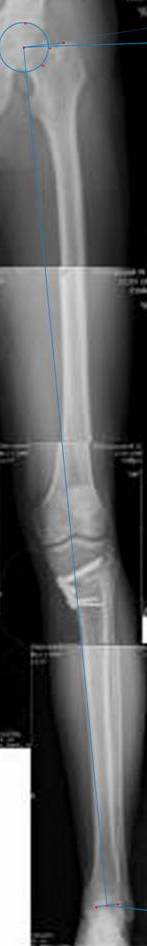

картинки оперированного пациента 40 лет, травма в 2006 году.

оперирован 06.11.2009г - корригирующая остеотомия большеберцовой кости.

Скажите, действительно ли эта остеотомия высокая?

Согласен с Вами, эта "скажем" не высокая остеотомия

Я картинку собрал с некоторыми погрешностями, если провести отвес от центра вращения головки бедра до середины голени (на пациенте),то имеется небольшой вальгус (гиперкоррекция)конечно она (гиперкоррекция) не достигает 10 гр, но 5 гр она достигает.

Проблема как сделать рентгеновские снимки а потом их совместить правильно, кто знает как решить этот вопрос. Ведь стандартные размеры рентгенкассет, оснащенные наши стационары отснять всю конечность с трех попыток!

Уважаемый д-р Батал Шушания,

К сожалению, не очень удачный пример. Если верить Р-граммам, имеет место быть дисплазия мыщелков бедренной кости с наклоном суставной линии. Это уже создает сложности получения хороших отдаленных результатов. Кроме того, по классике, необходима гиперкоррекция с созданием вальгуса 7-10 градусов для максимальной разгрузки медиального отдела КС. Если верить укладке, то линия сустава имеет четкий варусный наклон, поэтому результат операции м.б. кратковременным. В этих случаях показана двойная остеотомия бедра и тибии.

Отправитель: Alexander Artemiev 10 Ноябрь 2009, 15:54

Здравствуйте, дорогие коллеги.

Впечатление искажает неправильная укладка.

Если сделать правильно, то видно, что бедренная кость в порядке, а цель остеотомии (низкой, кстати), не достигнута вовсе.

Сохраняется варус. Для того, чтобы создать вальгусную гиперкоррекцию, не моделируя при этом откровенный Х голени, можно сделать медиализирующую остеотомию.